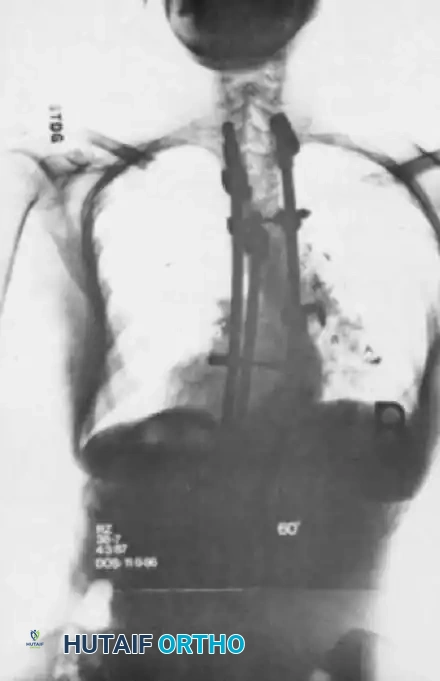

Fig. 41-13 Preoperative standing AP radiograph demonstrating a severe, decompensated adult idiopathic scoliotic curve. Note the significant coronal translation and rotatory subluxation at the lumbar levels.

- AP View: Used to measure the Cobb angle, assess Nash-Moe vertebral rotation, and identify coronal decompensation (C7 plumb line offset from the central sacral vertical line).

- Lateral View: Essential for evaluating PI, PT, SS, LL, TK, and SVA. The PI-LL mismatch is the most critical calculation for preoperative planning.

Fig. 41-15 Postoperative AP radiograph demonstrating a long posterior spinal fusion construct utilizing high-density pedicle screw fixation to correct a severe coronal deformity.

Fig. 41-16 Postoperative lateral radiograph showing restoration of lumbar lordosis and global sagittal balance. Note the robust pelvic fixation utilizing iliac screws extending distal to the sacrum.